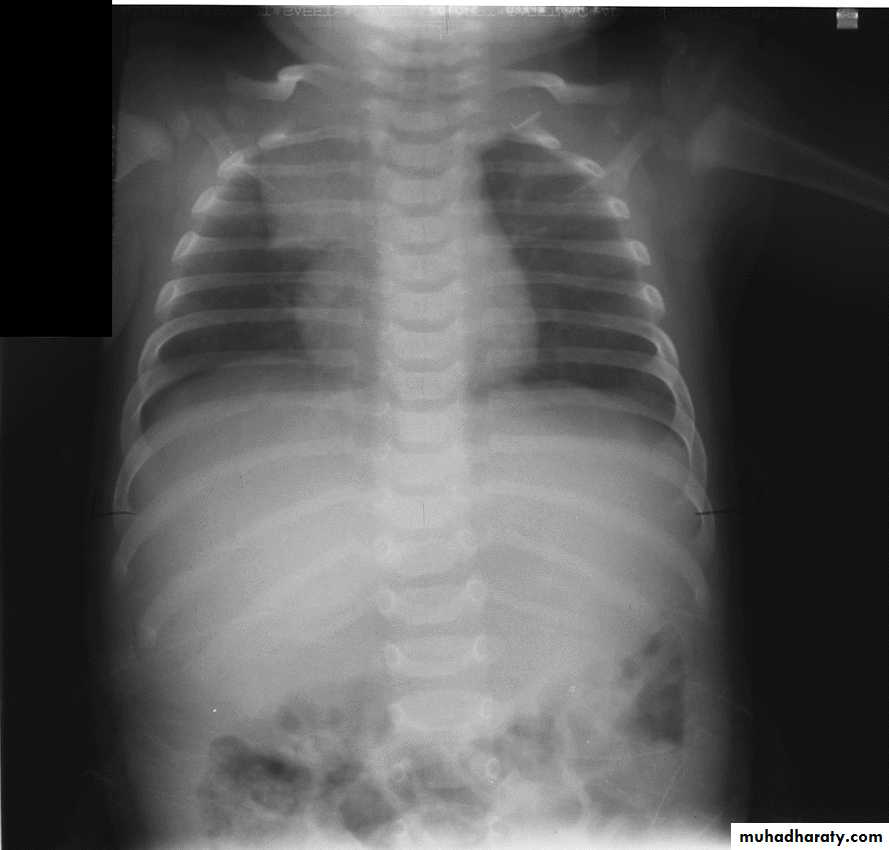

Anterior ends of ribs & clavicles directed downwardAP(infants & bed ridden patients )

anterior ends of ribs & clavicles directed upwardPA VERSUS AP PROJECTION:

Avoid the magnification of the heart.Protect the radio-sensitive organs, lens of the eye, thyroid gland, breast tissue in females and gonads.

Displace the scapula and clavicles away from the lung shadow.